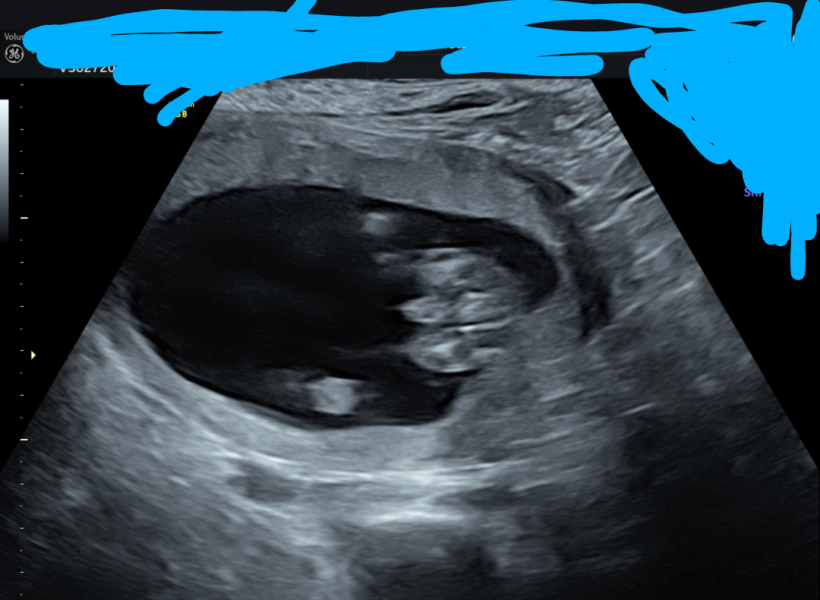

Can anyone see nub on scan image? Not sure what to look for

Not sure if what I'm looking at is the nub but from that and skull shape i'd say boy 💙

Boy nub for sure

No I definitely agree not the nub but I don't believe in skull theory there's no scientific evidence but thanks for your gender guess anyway.

I think all these theories are just a bit of fun, don't you? With the skull shape, I'm just comparing to my 2 girls scans as it looks different.

Guesses think it's quite obvious?